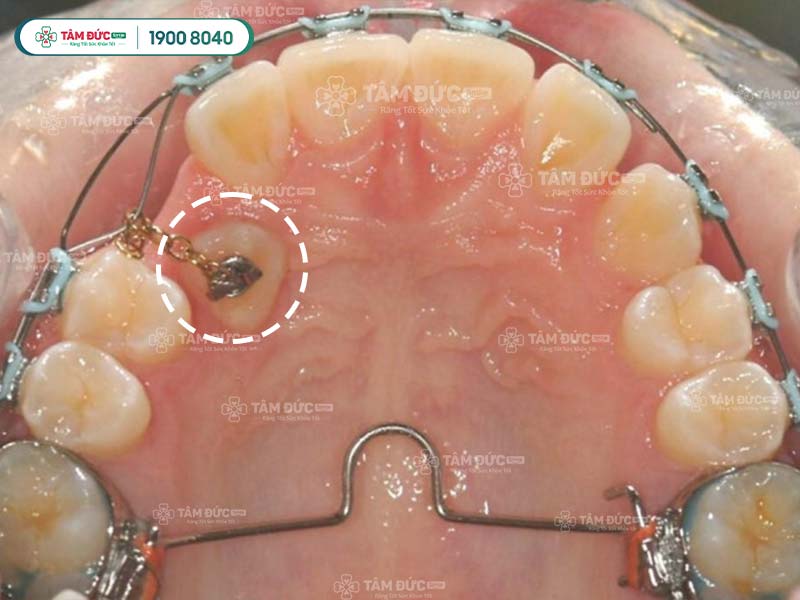

5.2. Giai đoạn 2: Phẫu thuật bộc lộ răng

Nếu răng ngầm nằm sâu trong xương hàm, bác sĩ cần thực hiện phẫu thuật bộc lộ răng để lộ phần thân răng ra ngoài. Phẫu thuật này được thực hiện dưới gây tê tại chỗ, nên sẽ không cảm thấy đau đớn.

5.3. Giai đoạn 3: Kéo răng

Sau khi răng đã được bộc lộ, bác sĩ sẽ sử dụng hệ thống lực kéo để di chuyển răng lên trên cung hàm. Có 3 loại hệ thống lực kéo chính: